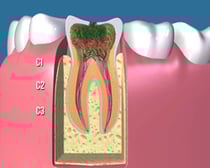

C3:

c3

かなり虫歯が進行してしまって、歯の神経と呼ばれる歯髄にまで虫歯が達してしまった状態です。熱い物で痛みが出たり、場合によってはひどくズキズキ痛むことも少なくありません。

この場合、歯を大きく削って歯の神経を除去する難易度の高い根管治療や大きく歯を削ってすっぽりかぶせる治療が必要になり、その後多くの場合はかぶせ物で修復することになります。

C4:

c4

虫歯によって、歯の頭の部分がほとんど崩壊してしまった状態です。残っている歯根の状態によっては抜歯になることも多くあります。歯を残す場合も、難易度の高い根管治療が必要で、歯根に深く維持を求める「差し歯」になります。治療後も「差し歯」によって歯根が割れるリスクが残ります。